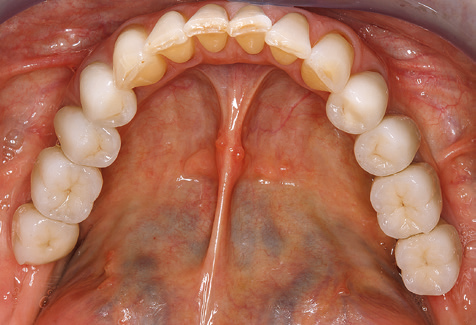

Eine 52-jährige Patientin stellte sich nach Zahnverlust im 3. Quadranten erstmals 2004 vor. Sie hatte den Wunsch nach einer prothetischen Neuversorgung. Im Rahmen der parodontologischen und radiologischen Diagnostik zeigte sich ein ausgeprägter parodontologischer Behandlungsbedarf. Die Zähne 48, 28, 27 zeigten zudem eine infauste Prognose und wurden entfernt (Abb. 1). Nach der erfolgreich abgeschlossenen systematischen PARTherapie wurde eine festsitzende implantatprothetische Versorgung mit Insertion von fünf Implantaten in Regio 35, 36, 37 und 46, 47 durchgeführt. Die prothetische Versorgung der natürlichen Zähne erfolgte mit verblendeten Zirkonoxidkeramikkronen, die Implantate wurden mit zweiteiligen individuellen Zirkonoxidabutments und ebenfalls verblendeten Kronen aus einer Zirkonoxidkeramik versorgt (Cercon base colored, Dentsply Sirona Lab). Die definitive Insertion der prothetischen Versorgung erfolgte im Jahr 2005.

Aufgrund der bestehenden parodontalen Vorerkrankung erfolgte die unterstützende Parodontaltherapie (UPT) in den ersten Jahren in einem DreiMonatsIntervall. Dabei zeigte die Patientin eine hohe Motivation und gute Compliance. Bei den jährlich erhobenen Sondierungsbefunden zeigten sich stabile parodontale Verhältnisse mit einem BOPIndex unter fünf Prozent. Aufgrund der stabilen parodontalen Situation und der guten Mitarbeit der Patientin wurde ab dem sechsten Jahr der prothetischen Funktionsphase das Recallintervall auf halbjährlich umgestellt. Auch mit diesem veränderten Recallintervall zeigten sich bei der jeweils jährlichen Aufnahme des Parodontalstatus stabile parodontale Verhältnisse, ohne Zunahme der Sondierungstiefen und einem BOPIndex unter fünf Prozent (Abb. 2a und b).

Im Rahmen der ZehnJahresKontrolle zeigten sich keine Hinweise auf einen fortschreitenden parodontalen Attachmentverlust oder einen periimplantären Knochenverlust (Abb. 3).

Die Patientin befindet sich weiterhin in einem halbjährlichen Intervall für die UIT. Nachfolgend werden am Beispiel dieser Patientin die einzelnen Arbeitsschritte einer strukturierten UPTSitzung aufgezeigt, so wie sie nahezu unverändert über den gesamten Funktionszeitraum von immerhin zwölf Jahren durchgeführt wurden. Natürlich wurden über diesen Zeitraum einige neue Materialien und Geräte in das Konzept integriert. In diesem klinischen Fallbericht wird das aktuelle Material und Gerätekonzept präsentiert.

Für den klinischen Langzeiterfolg des parodontal kompromittierten Patienten ist die standardisierte und regelmäßige risikoadaptierte Betreuung im Rahmen der UPT der zentrale Baustein des Behandlungserfolgs. Dies gilt in besonderer Weise für Patienten, die nach erfolgreich abgeschlossener parodontaler Sanierung mit Implantaten versorgt wurden (Abb. 11a und b).